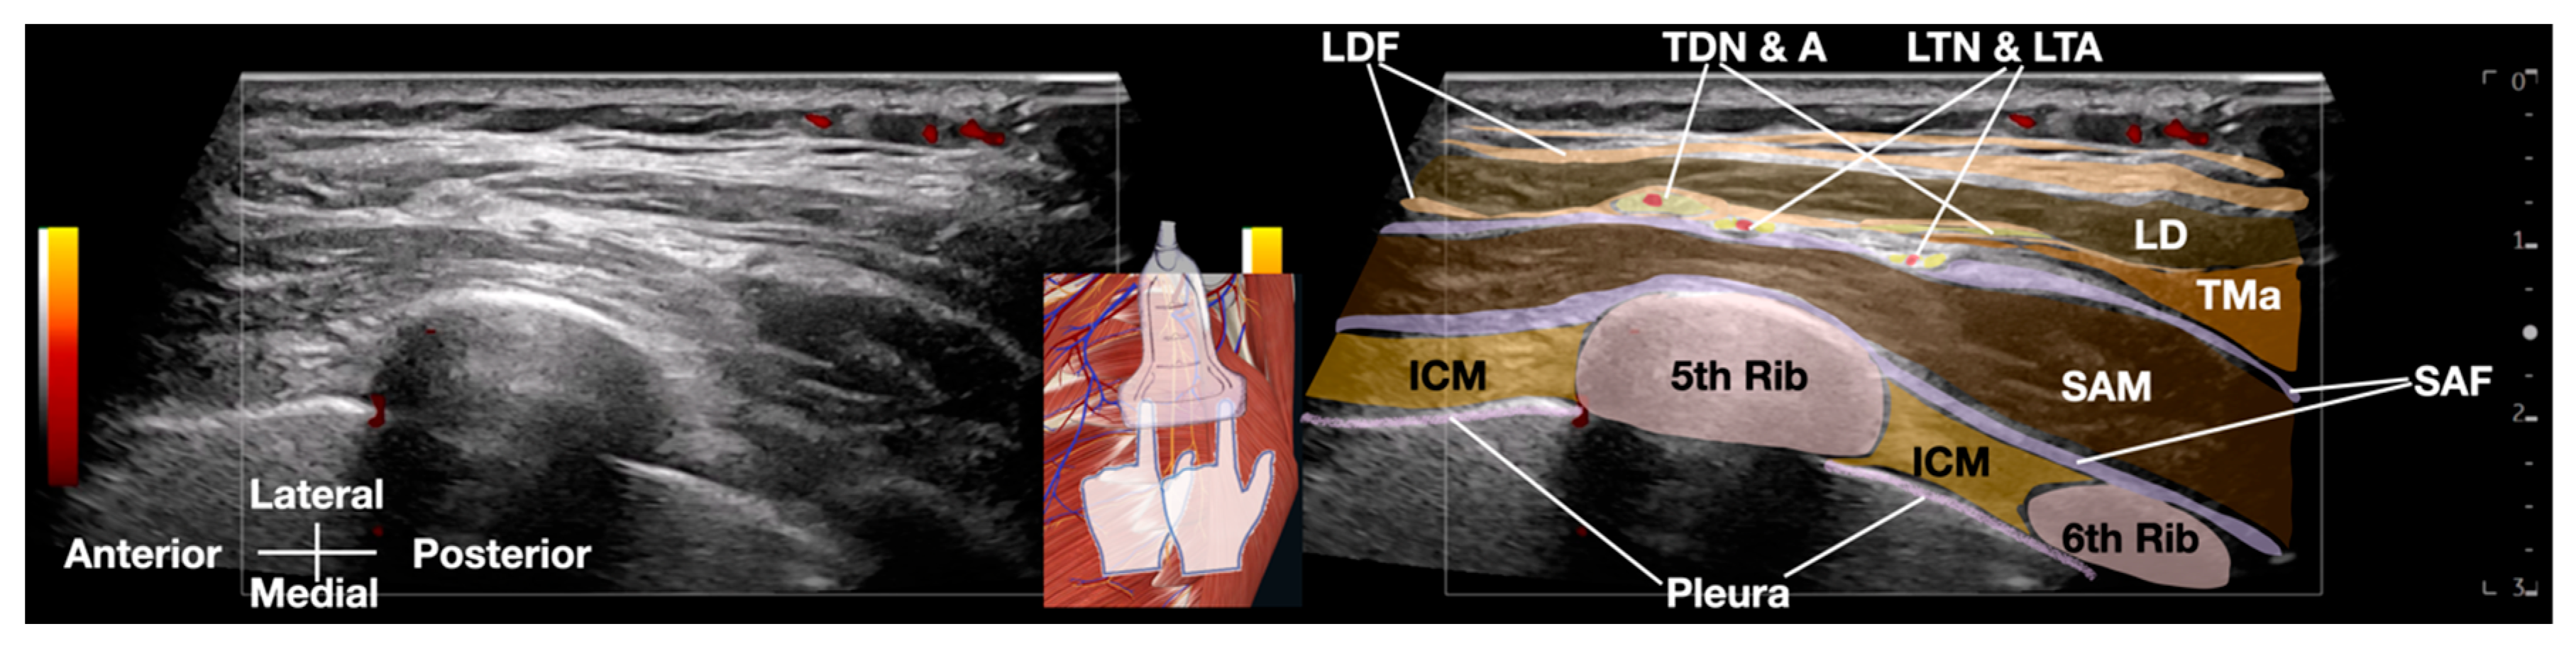

Anatomy of SAM and LTN

2.2. Ultrasound-Guided Hydrodissection of Long Thoracic Nerve: Methodology

| LDF | Latissimus Dorsi Fascia |

| LTN | Long Thoracic Nerve |

| LTA | Lateral Thoracic Artery |

| SAM | Serratus Anterior Muscle |

| SAF | Serratus Anterior Fascia |

| TDN | Thoracodorsal Nerve |

| TMa | Teres Major Muscle |